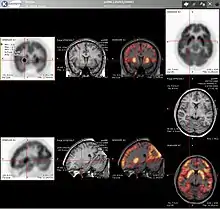

Neuroimaging

Neurology

PET imaging with oxygen-15 indirectly measures blood flow to the brain. In this method, increased radioactivity signal indicates increased blood flow which is assumed to correlate with increased brain activity. Because of its 2-minute half-life, oxygen-15 must be piped directly from a medical cyclotron for such uses, which is difficult.[17]

PET imaging with FDG takes advantage of the fact that the brain is normally a rapid user of glucose. Standard FDG PET of the brain measures regional glucose use and can be used in neuropathological diagnosis.

Brain pathologies such as Alzheimer's disease (AD) greatly decrease brain metabolism of both glucose and oxygen in tandem. Therefore FDG PET of the brain may also be used to successfully differentiate Alzheimer's disease from other dementing processes, and also to make early diagnoses of Alzheimer's disease. The advantage of FDG PET for these uses is its much wider availability. Some fluorine-18 based radioactive tracers used for Alzheimer's include florbetapir, flutemetamol, Pittsburgh compound B (PiB) and florbetaben, which are all used to detect amyloid-beta plaques, a potential biomarker for Alzheimer's in the brain.[18]

PET imaging with FDG can also be used for localization of "seizure focus". A seizure focus will appear as hypometabolic during an interictal scan.[19] Several radiotracers (i.e. radioligands) have been developed for PET that are ligands for specific neuroreceptor subtypes such as [11C]raclopride, [18F]fallypride and [18F]desmethoxyfallypride for dopamine D2/D3 receptors; [11C]McN5652 and [11C]DASB for serotonin transporters; [18F]mefway for serotonin 5HT1A receptors; and [18F]Nifene for nicotinic acetylcholine receptors or enzyme substrates (e.g. 6-FDOPA for the AADC enzyme). These agents permit the visualization of neuroreceptor pools in the context of a plurality of neuropsychiatric and neurologic illnesses.